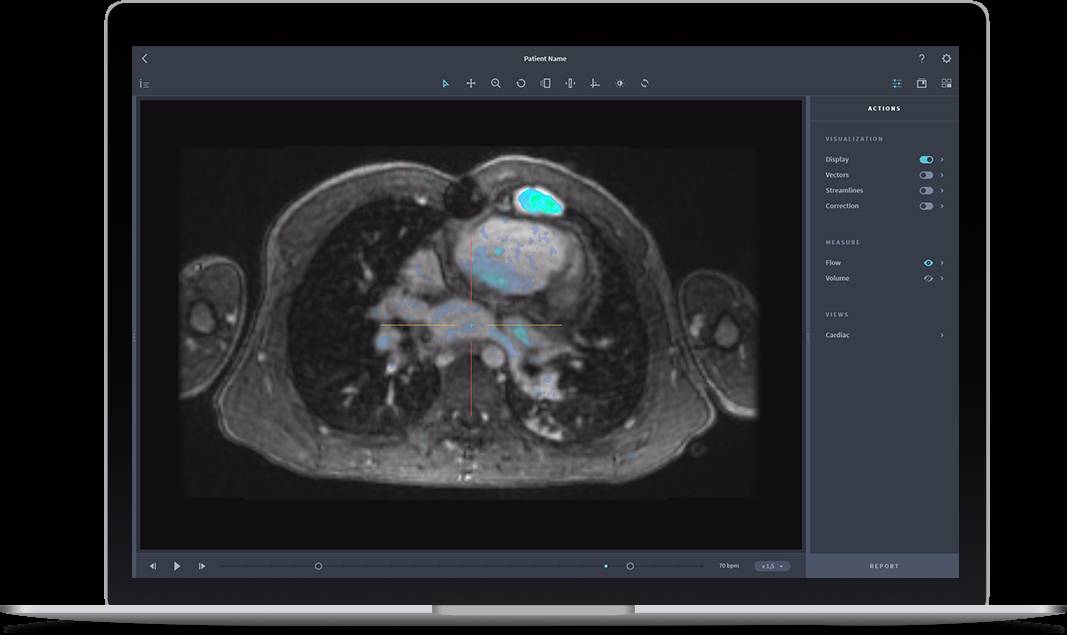

这个被FDA首次批准投入临床的的机器学习应用是Arterys的医学成像平台,帮助医生诊断心脏问题。它使用一个自学的人工神经网络,从从迄今为止的1,000个病例,并逐渐录入新的病例,进行检查和学习,逐渐提高在对于心脏工作原理的认识

目前这个平台的目标是帮助医生了解心脏的生理机制,通过准确测量每个心室的体积,允许更准确的健康评估。其他人计划正在开展。

图片来自Arterys官网

在输入1,000个病例作为训练数据后,Arterys Cardio DL运行监督学习算法,并基于数据中发现的关联性总结出约1000万条规则。 其目的是在没有人工干预的情况下能够识别并研究问题。 然而,它的目标不是取代医生,Beckers承诺道,而是为他们提供有助于他们更有效地工作的工具。

1)云:可视化(最快100fps),量化(采用GPU,并行化等大量计算工具和技术),机器学习(针对医学影响处理

2)4D flow:通过MRI,展示体内血液流程的可视化和量化的首个技术